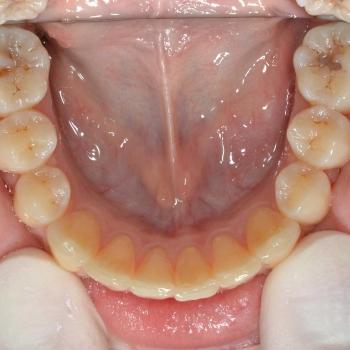

Eszter a kezelés megkezdésekor headgear típusú fogszabályozó készüléket kapott annak érdekében, hogy a felső nagyőrlőket hátrafelé mozgassuk, illetve, hogy a keletkező rést felhasználjuk a kisőrlők és a szemfogak hátramozdítására is. Az így felszabadult hely az Eszter által választott hagyományos fém fogszabályozó segítségével felhasználható volt a metszőfogak elrendezéséhez, azok túlzott előredőlése nélkül.

A kezelés eredményeként minden kiindulási problémát sikerült megoldani és egy esztétikailag és funkcionálisan is szép mosolyt létrehoznunk.